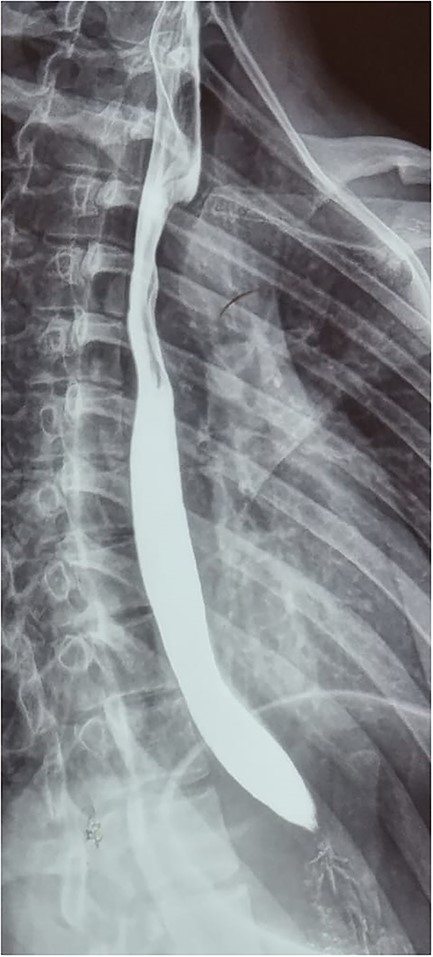

Patient is an 18-year-old female without past medical history. She suffered a 2-month gradually progressive dysphagia accompanied by mild reflux. At first, it was treated as gastroesophageal reflux disease (GERD), and proton pump inhibitors were given with poor results. Dysphagia became so severe at one point that she could not drink any liquid, including saliva; therefore, she presented at our hospital. Clinical examination, including palpation of her peripheral pulses, was unremarkable; therefore, additional exams were required. An esophagogram (Fig. 1) revealed an extrinsic compression above the level of the aortic arch. With these findings, a computed tomography angiography was requested and demonstrated aberrant anatomy of the aortic arch; the carotid arteries arise from one common trunk, the truncus bicaroticus, and an ARSA was found compressing the esophagus as it crossed behind it. There was no evidence of Kommerell’s diverticulum, aneurysmal dilation, or other abnormalities (Fig. 2A and B).

Esophagogram revealing an extrinsic compression above the level of the aortic arch.